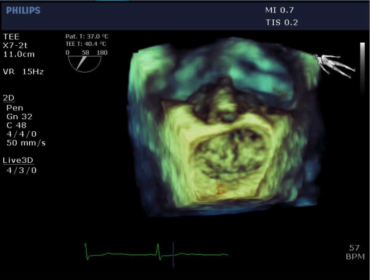

Per intervenire rapidamente è necessario un sistema ecografico portatile Non è semplice riuscire a ottenere dati diagnostici da esami effettuati con sistemi portatili. Con CX50 ora potrete avere ovunque la qualità necessaria per formulare diagnosi affidabili. È il sistema ecografico stesso ad andare dal paziente e può essere trasportato anche in sala operatoria, unità coronarica, unità di terapia intensiva, anche neonatale o pediatrica, presso ambulatori di screening o al pronto soccorso. La qualità delle immagini di CX50 lo rende ideale per i pazienti in condizioni critiche, quando lo spazio è limitato dalla presenza di molte apparecchiature e servono risposte rapide.